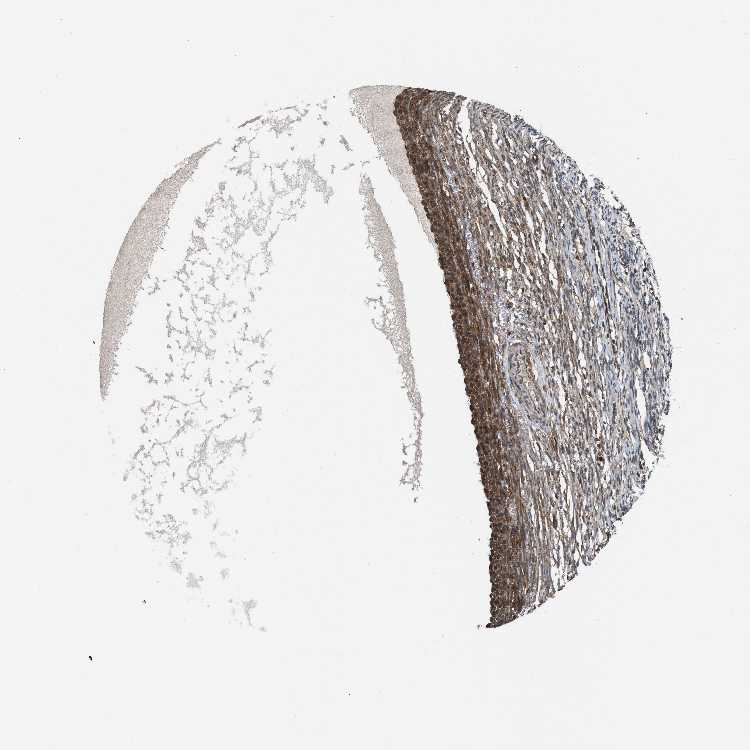

OVARY - Antibody stainingi

Antibody staining in the annotated cell types in the current human tissue is reported as not detected, low, medium, or high, based on conventional immunohistochemistry profiling in selected tissues. This score is based on the combination of the staining intensity and fraction of stained cells.

Each image is clickable and will lead to virtual microscopy that enables deeper exploration of all samples and also displays staining intensity scores, fraction scores and subcellular localization as well as patient and tissue information for each sample.

Antibody HPA021197

Follicle cells High

Ovarian stroma cells Medium